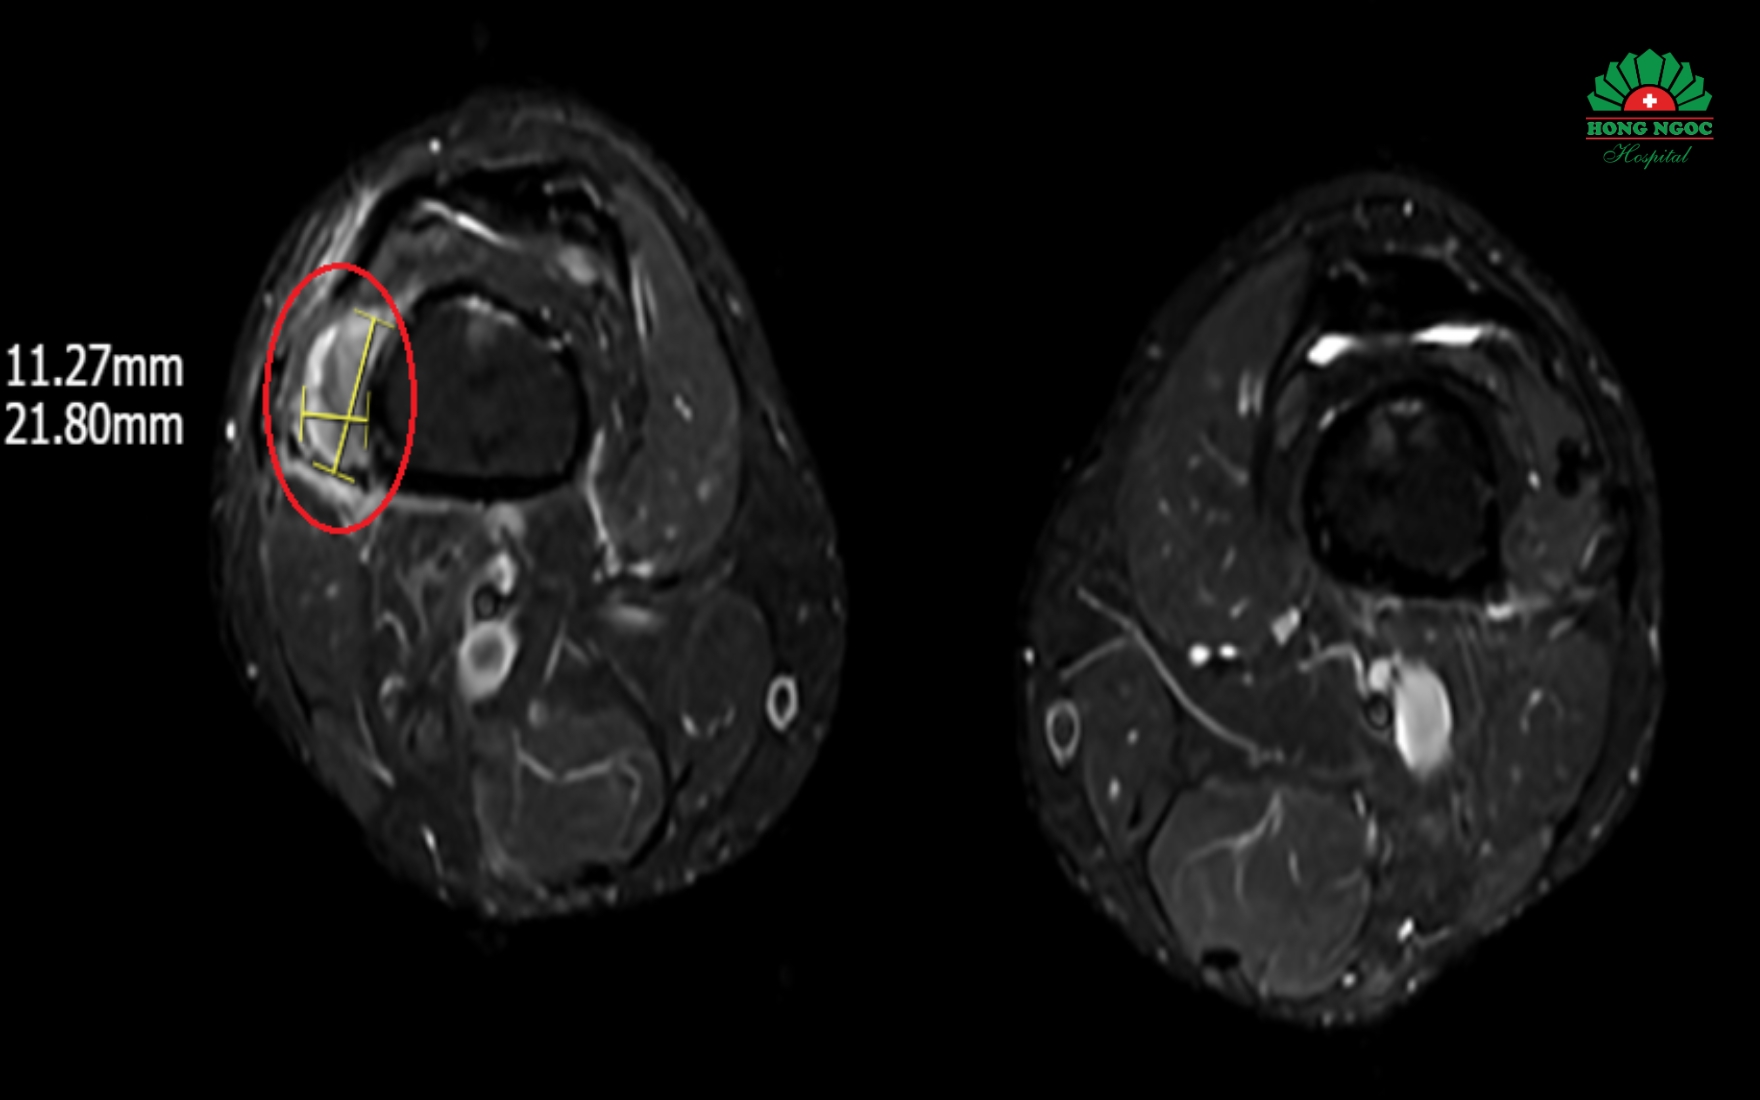

MRI 영상에 나타난 우측 허벅지 아래 연부 조직 종양

반 석사 의사는 다음과 같이 설명합니다. “종양의 정확한 위치를 파악하는 것입니다. 종양을 제거해야만 뼈를 약하고 부서지기 쉽게 만드는 인산 결핍의 근본적인 원인을 해결할 수 있기 때문입니다. 그러나 진단 과정은 많은 어려움이 따릅니다. FGF23 분비 종양은 대부분 양성 종양이며 크기가 작고 통증이나 부종을 유발하지 않습니다. 특히 이 종양은 신체 어느 부위든 나타날 수 있습니다. 정확한 진단을 위해서는 혈액 내 FGF23 수치를 측정해야 하지만, 현재 베트남에서는 이 검사가 불가능합니다. 따라서 우리는 환자에게 방사성 추적자를 이용한 전신 PET/CT 촬영을 MRI 및 초음파 검사와 함께 처방했습니다. 마침내, 환자의 오른쪽 허벅지 아래 연조직에서 약 1~2cm 크기의 종양을 발견했습니다.”